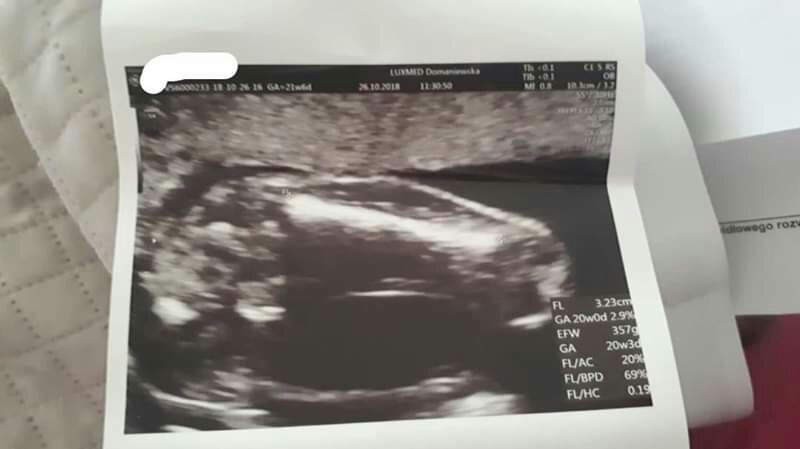

Witam w 19 tygodniu ciąży dowiedziałam się ze będę miała dziewczynkę w 20 tyg okazało się jednak , że to chłopak. Sama już nie wiem bo na jednym usg widać na pewno dziewuche a na drugim chłopca. Może to pempowina ?? Może ktoś mi pomoże rozwiązać ta zagadkę

czy to brzuszek , nozki I siusiak ? Mam juz dwoch chlopcow I cicho licze jeszcze na dziewuszke